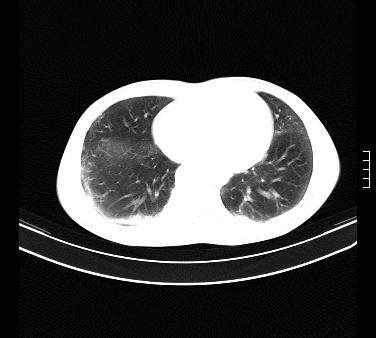

患者,男,17岁,系我院急诊科收治的一例百草枯中毒患者,做ct检查时,距离服药的时间为3天。上传与大家分享

补充:百草枯进入人体内主要分部于肺和骨骼,肺部损伤24小时内出现水肿,2-3天内出现急性呼吸窘迫综合征,1-2周内出现肺纤维化。(引自陈灏珠,实用内科学12版)